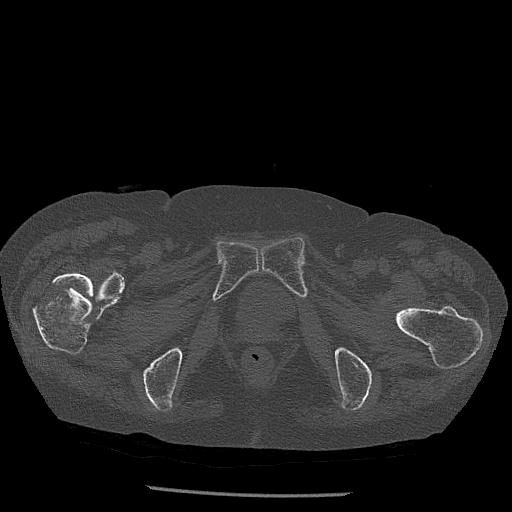

100703 1/27 両股正面+軸 1/29 両股正面+軸 94歳女性 パンソンロン